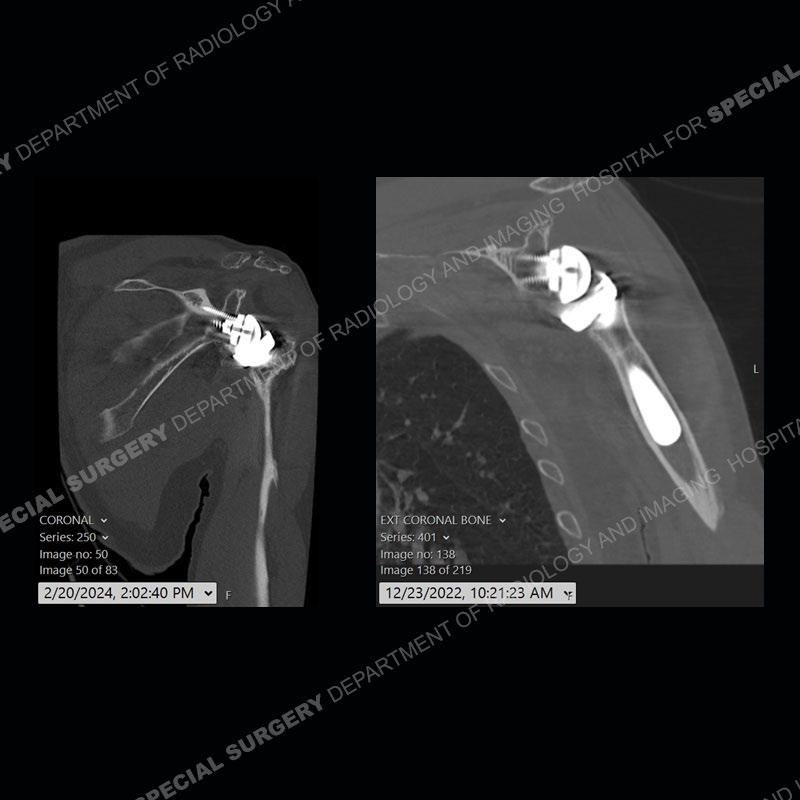

When comparing the radiographs, there is a slight change in the alignment in the components of the prosthesis. On the current radiographs, a radiolucent, crescentic focus is present at the level of the glenoid. When comparing the CT exams, there is a change at the alignment of the glenosphere and the humeral component and now a direct apposition of the components. On the current CT, the radiolucent, crescentic focus is again identified.

If comparison radiographs are present, subtle changes can be made more apparent. Instead of a space between the glenosphere and the humeral tray, there is a direct contact, and there may be an overall change in the alignment at the articulation. The displaced, radiolucent polyethylene liner depending on location can be seen on the radiographs, as in this case. At times, the liner may overlie other structures making identification very difficult on radiographs, but it should almost always be able to be identified on CT (as shown in this example as well). This patient is scheduled for revision procedure.